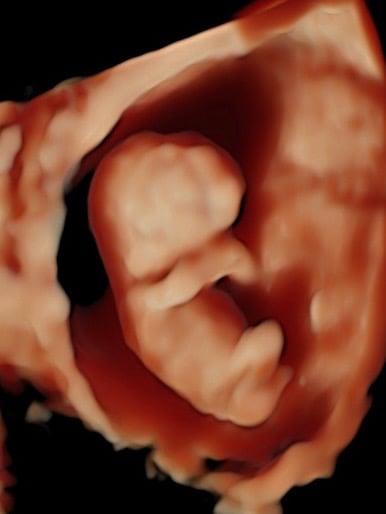

Monitoreo y cuidado especializado para el bienestar de tu bebé durante el embarazo.

Galería Neomamá

Explora momentos especiales y servicios para mamás y bebés aquí.